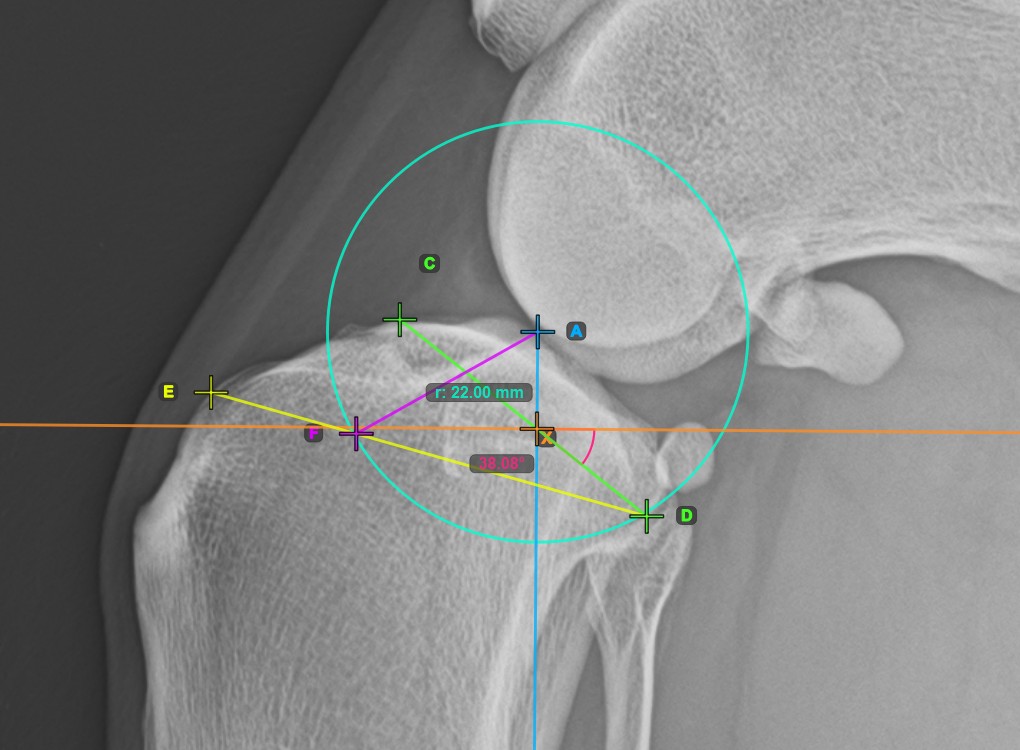

Fejezze be a TPA szög mérését a tibia fejének (tibia plató) legalacsonyabb pontjának megjelölésével. A TPA szög automatikusan kiszámításra kerül a tibia platón lévő két pontot összekötő vonal és a tibia hosszanti tengelyére merőleges vonal közötti szögként.

A lenti kép a tibia plató legalacsonyabb pontjának szokásos elhelyezkedését és a TPA szög automatikusan kiszámított értékét ábrázolja.